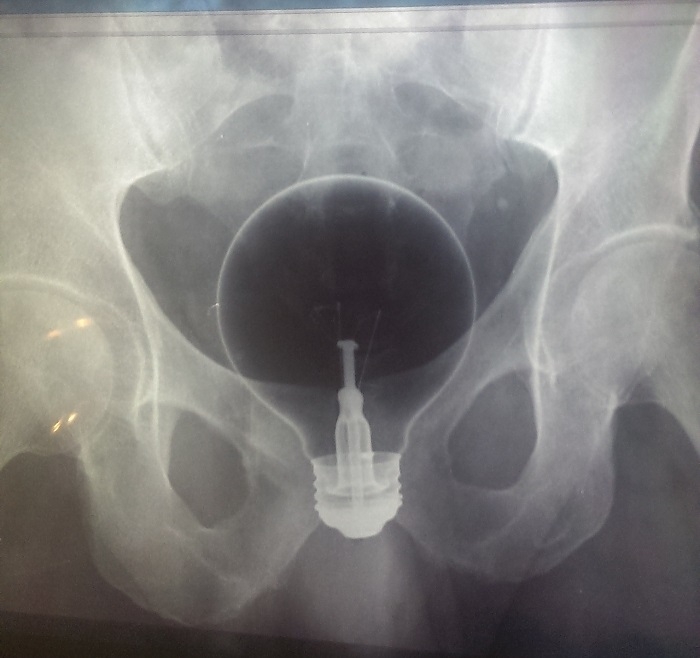

Malum Bölgelerine Kazayla Giren Nesneler Sonucu Acile Kaldırılmış İnsanların 15 Röntgen Görüntüsü  Bu nesnelerin orada olmasının mantıklı hiçbir alakası yok. Büyük ihtimalle bir kaza sonucu bu durum oluşmuştur. Aksini düşünmek bile istemiyorum. Foto Galerimizin devamını görmek için Lütfen sonraki sayfaya geçiniz..